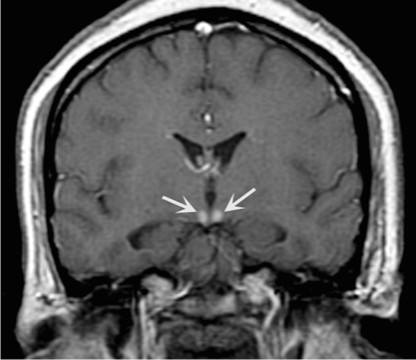

Характерным является перивентривулярное поражение церебральных тканей в области III и IV желудочков, сильвиевого водопровода. Страдают преимущественно структуры ствола мозга и промежуточного мозга, червь мозжечка, медиодорсальное ядро таламуса. С патологией последнего связывают сопровождающие синдром Гайе-Вернике расстройства памяти.

В половине случаев синдром Гайе-Вернике сопровождается генерализованным замедлением волн при ЭЭГ. РЭГ зачастую определяет диффузное снижение церебрального кровотока. КТ головного мозга, как правило, не регистрирует патологические изменения в церебральных тканях. МРТ головного мозга позволяет выявить гиперинтенсивные области в медиальных ядрах таламуса, мамиллярных тельцах, стенках III желудочка, ретикулярной формации, сером веществе, окружающем сильвиев водопровод, крыше среднего мозга. Зоны поражения склонны накапливать контраст, вводимый при проведении дополнительного контрастирования в ходе МРТ. В перечисленных областях могут определяться петехиальные кровоизлияния и признаки цитотоксического отека.